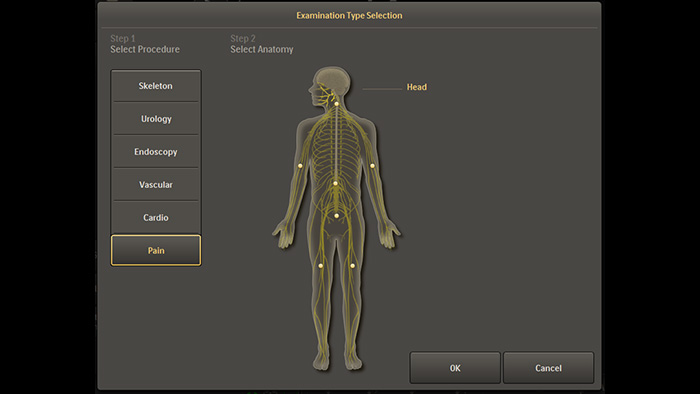

Configuración personalizada del examen del dolor

Los ajustes únicos del examen de gestión del dolor preconfigurados permiten a los usuarios organizar el sistema con facilidad durante los procedimientos de intervención para el tratamiento del dolor.